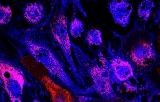

TERT probe for FISH CE/IVD - Brain and neural pathology

The TERT (telomerase reverse transcriptase, a.k.a. EST2, TCS1) gene encodes the reverse transcriptase component, a catalytic domain of the enzyme telomerase. Telomerases are necessary to maintain the ends of chromosomes and are inactive in the majority of somatic cells but active in cancer cells. Remodeling of the genomic context, due to 5p15.33 rearrangements, abrogates transcriptional silencing of the TERT gene. TERT translocations are the second common aberration found in neuroblastomas. These translocations are observed either in a 50 kb region proximal or more rarely in a 40 kb region distal to the gene. Molecular genetic studies showed that rearrangements of the chromosomal region 5p15.33 occur exclusively in high-risk neuroblastomas. Therefore, TERT rearrangements are considered to define a sub-group of high-risk neuroblastomas with a poor prognosis. Rearrangements of TERT are found in chromophobe renal cell carcinomas, non-Hodgkin lymphomas, and mantle cell lymphomas. FISH is a suitable tool for the detection of these TERT rearrangements and thus may be of prognostic relevance.